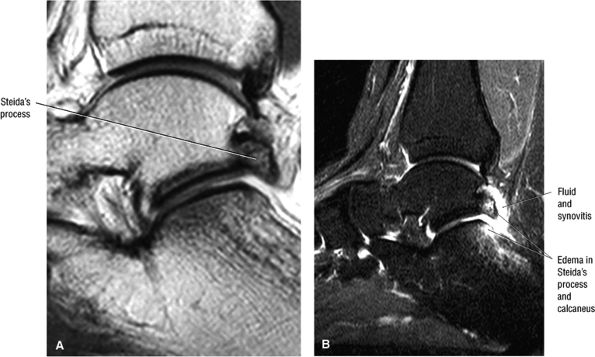

FIGURE 5.25 ● Sagittal anatomy of the ankle and foot. (A) The origins of the anterior talofibular ligament and posterior talofibular ligament are identified arising from the anterior and posterior distal tip of the lateral malleolus. From the origin, the full course of these ligaments can be followed medially on successive sagittal images to their insertions on the anterior and posterior talus. (B) The vertical course of a long segment of the peroneus longus and brevis tendons is often visualized on a single sagittal image through the tendons. This image is useful to further characterize tendinosis and longitudinal tears or splits, and for measuring the gap between completely ruptured tendon fragments. (C) The anterior process of the calcaneus is a common location for fractures that are occult on plain film. They are optimally visualized in the sagittal plane on MR exams. (D) In addition to occurring at the tibiotalar joint, degenerative arthrosis is also commonly found at the posterior subtalar, calcaneocuboid, and talonavicular joints. The cartilage surfaces and subchondral bone at these articulations are optimally visualized in the sagittal plane. (E) The presence of an os trigonum posterior to the talus predisposes certain athletes with a predilection for plantarflexion to the os trigonum syndrome. This is diagnosed on sagittal MR images when edema is visualized within the os trigonum and extends across the synchondrosis into the posterior talus. (F) Abnormal signal in the sinus tarsi manifests as high signal on FS fluid-weighted sequences and low signal on non-FS sequences. This abnormal signal may suggest, but is not specific for, inflammation in the sinus tarsi. Other causes of abnormal signal in the sinus tarsi, which may be incidental and asymptomatic, include extension of joint fluid from the posterior and middle subtalar joints, extension of generalized edema throughout the soft tissues of the ankle from stasis or other causes, enlarged vessels, and ganglion cysts.(G) Two potential causes of an incidental “mass” palpated on physical examination about the Achilles tendon are a low-lying soleus muscle and an accessory soleus muscle, both of which are diagnosed by MR imaging. The normal soleus muscle extends to about the proximal one third or one half of the Achilles tendon. A low-lying soleus will extend to the distal third of the tendon. An accessory soleus is present when there is an extra muscle in the pre-Achilles fat, usually extending to the distal third of the tendon, often near the distal insertion. (H) In the setting of a complete Achilles tendon rupture, the location of the tear may be at the myotendinous junction, mid-tendon, distal tendon, or tendon insertion at the os calcis. In addition, the tear is characterized as transverse or oblique longitudinal. In the case of transverse tears, the distance between the tear and tendinous insertion at the calcaneus is measured. Also, the length of good-quality tendon stump at the calcaneal insertion is measured, since the surgeon often uses the distal stump in the surgical reconstruction or repair. (I) The anteromedial aspect of the tibiotalar joint is a common location for the formation of large osteophytes, which extend anteriorly from the anteromedial tibia and talus. These may cause pain, limit the range of motion, or break off and form loose bodies within the tibiotalar joint. This spectrum of findings is part of the anteromedial impingement syndrome. (J) Ancillary findings at the plantar aponeurosis visualized on sagittal images include bone marrow edema within the inferior calcaneus, inferior calcaneal enthesophyte with marrow edema, and high signal within the flexor digitorum brevis muscle and fat that surround the plantar aponeurosis. These findings suggest active inflammation in the tissues surrounding the plantar aponeurosis. (K) The deltoid ligament is found on sagittal images by finding its origin extending off the bilobed medial malleolus. The medial course of the deltoid ligament components is followed over the next two or three successive sagittal images. (L) The vertical course of the tibialis posterior tendon and the flexor digitorum longus tendon is often visualized on a single image. Triangulating on tendon pathology in both the sagittal and axial planes aids in further characterizing tendon abnormalities.